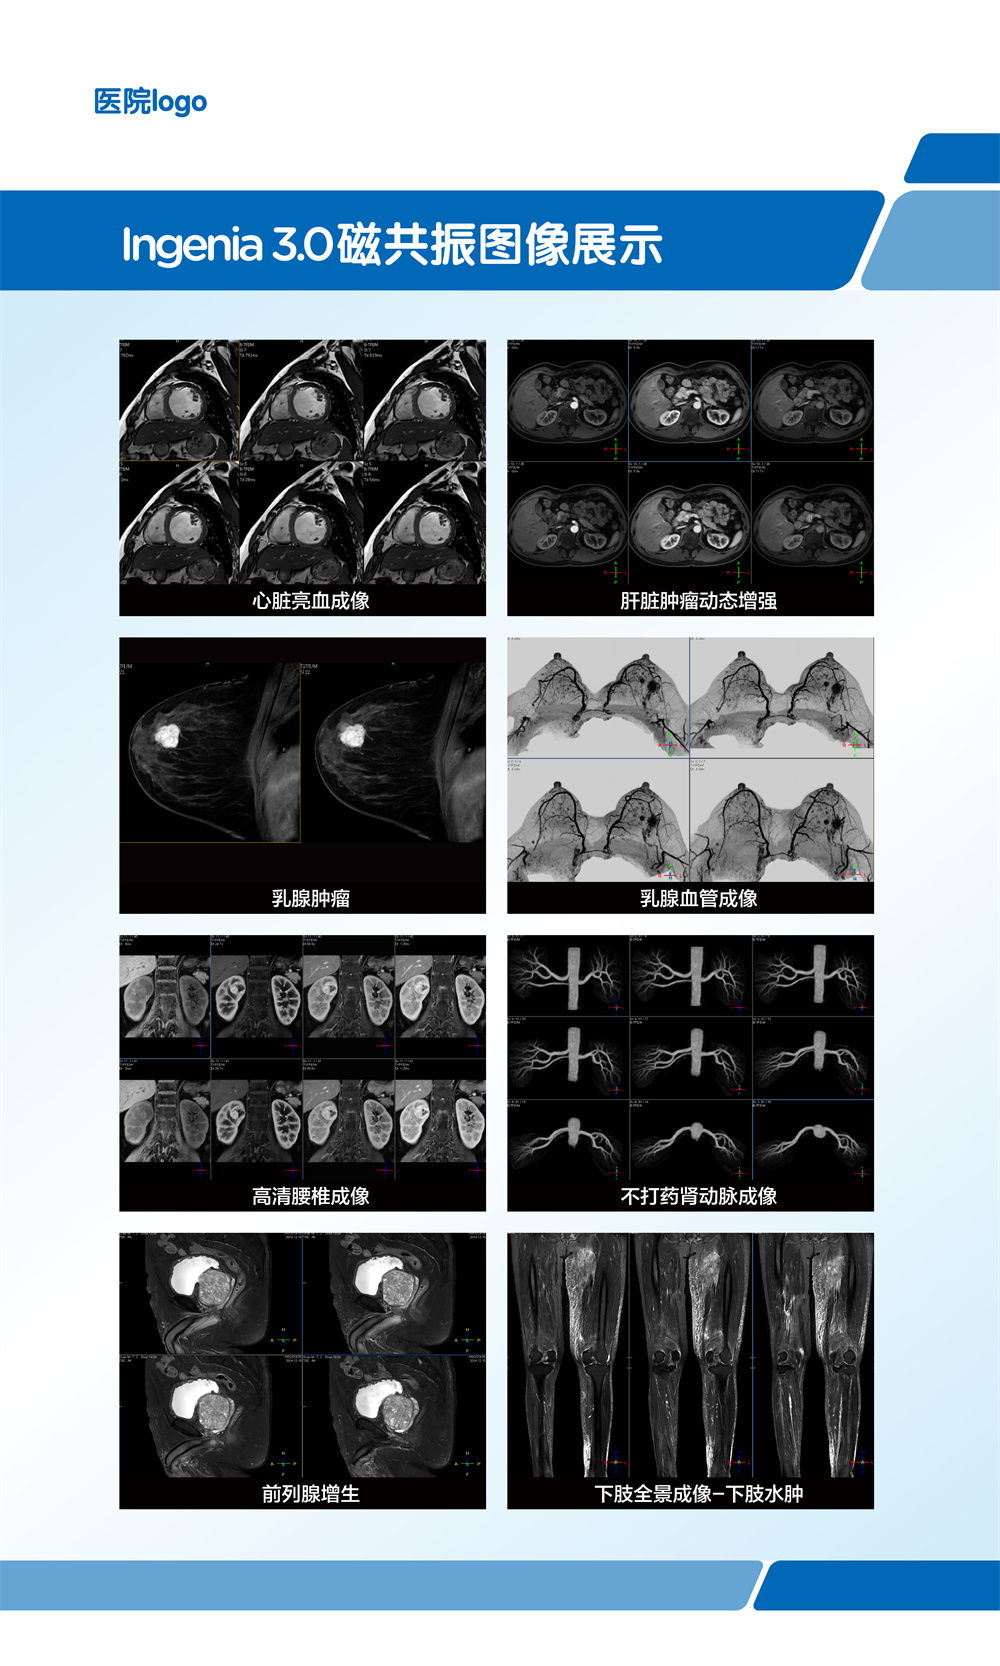

飞利浦大孔径光速Ingenia 3.0T磁共振是业内唯一同时具备"全数字高清成像平台和四维多源射频发射成像平台"的高端3T磁共振,具有病人检查舒适,扫描速度快,图像分辨率高的特点。在神经系统,骨肌系统,体部系统包括心脏和腹部等都有良好的应用和独到优势,为疾病的诊断及治疗提供更可靠、更丰富的信息,对于脑卒中和胸痛等中心的建设起到重要的作用。设备具备飞利浦独有的全数字线圈,可以实现三维全心不打药冠脉成像,无电离辐射和造影剂过敏风险,精准显示冠脉狭窄,有效排查临床无意义的冠脉狭窄(准确度达90%)。

磁共振冠状动脉检查无辐射,无需对比剂,对于缺血性心脏病,可以一次成像完整显示全心冠脉,便于直观诊断冠脉各分支情况。

在全身弥散加权成像的同时,可进行磁共振全身扫描,增加肿瘤检出敏感性。

临床应用范围:寻找恶性肿瘤原发灶;恶性肿瘤分期;全身转移灶筛查;淋巴结转移筛查;术后放化疗疗效监测;恶性血液肿瘤疗效观察;体检与肿瘤筛查。

第三代无损加速磁共振成像-压缩感知(CS-SENSE),最快 32 倍加速,已将绝大部分临床成像转化为快速高清容积扫描。